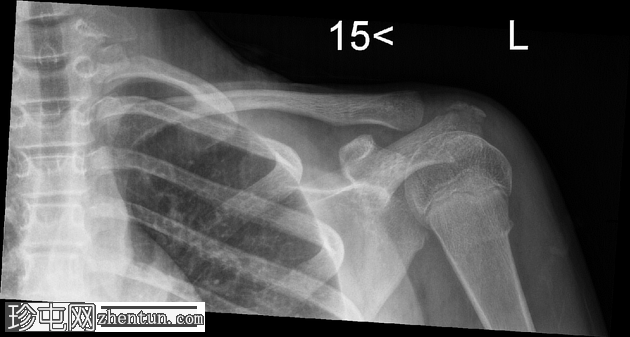

正位片

左侧肱骨近端干骺端可见环状骨折。皮质轮廓轻度不规则,呈环状弯曲,但无明显移位或成角。肱骨头与肩胛盂对位良好。

环状骨折,也称为环状骨折,是由轴向压缩引起的,导致皮质隆起或弯曲,但未发生完全断裂。由于儿童和青少年骨骼的柔韧性,这种类型的损伤在肱骨近端更为常见。骨折通常发生在干骺端-骨干交界处附近,即骨骼由松质骨过渡到致密骨的部位。

X线片上,表现为轻微的皮质不规则或弯曲,通常无移位或对位破坏。这些骨折本身较为稳定,通常采用保守治疗(例如用吊带或肩部固定器固定)即可良好愈合。早期识别至关重要,可以避免不必要的干预或漏诊更复杂的骨折。